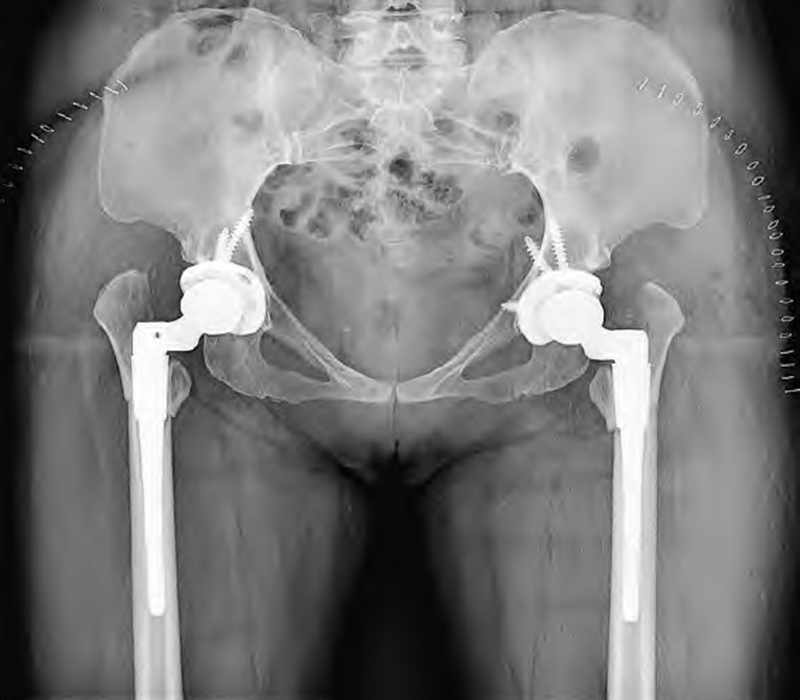

图1 术前骨盆正位DR:双侧CROWE Ⅳ型DDH,股骨头脱位高度>股骨头高度的100%。双侧均无假臼形成;真臼未能正常发育,髋臼浅小;股骨头小、不规则;股骨颈短,颈干角减小,偏心距减小,股骨近端骨皮质变薄,髓腔窄小变直,呈柱状,髓腔峡部位置相比正常股骨较高

图4 双侧THA术后DR:双侧臼杯均建立在真臼位置,假体适度内移,未额外骨移植,双侧均应用44mm生物型多孔臼杯和高交联聚乙烯内衬,搭配28mm陶瓷股骨头假体。股骨侧采用可调节前倾角的组配式假体,近端和远端均获得良好固定,双侧均采用转子下斜行截骨方式,截骨处固定可靠,未加用额外固定方式,假体匹配良好,双下肢基本等长

Crowe Ⅳ DDH股骨近端大小形态都与正常不同,股骨畸形可因脱位程度的增加而增加,有患者因股骨或骨盆矫形手术病史使得解剖更复杂。具体表现为股骨头小、不规则、失去圆形状态,股骨头软骨表面磨损严重,因假臼的反复刺激,股骨头周围可产生骨赘。股骨头位置高(相对于小转子),大转子-股骨头距离增大,股骨颈短,前倾增大,大转子后置,Sugano等发现DDH患者股骨颈前倾角平均增加10°~14°,但增大程度与脱位程度无关。此外,颈干角增大,偏心距减小,股骨前弓增大,近端骨皮质变薄,骨质脆性较大,弹性降低,远端股骨明显内旋。近端髓腔窄小变直,多呈柱状(烟囱型髓腔),髓腔峡部位置相比正常股骨较高,近端髓腔和峡部内径都较正常股骨小,前后径大于内外侧径(图1)。髓腔形态异常可随脱位程度增加而增加,小转子和峡部之间的骨干内产生扭转并与干骺端扭转异常无关。为此,需在术前通过影像学方法预测股骨髓腔直径、测定股骨前倾角、测定股骨偏心距。